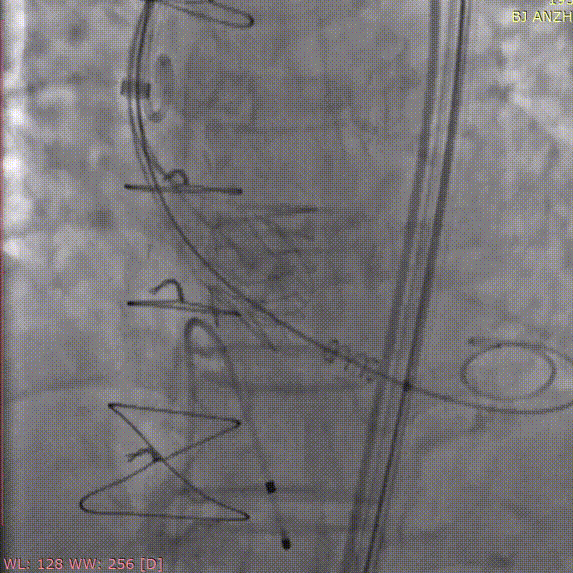

术前造影

定位件入窦

释放瓣膜

术后造影